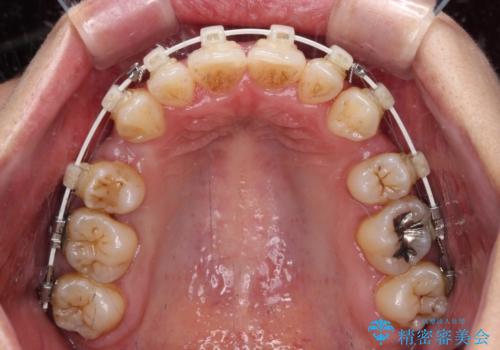

- 八重歯と上下前歯のでこぼこを気にして来院された患者様です。

上下前歯部叢生のスペース獲得のため、上下顎左右小臼歯各1歯(計4本)を抜歯して、ワイヤー装置にて矯正治療を行うこととしました。

上下の正中位置が大きくずれていたため、上下正中が合わないまま終了することが予想されましたが、思っていた以上にスムーズに歯が移動し、満足いただける仕上がりとなりました。